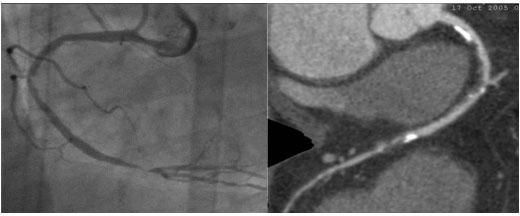

64排螺旋CT冠狀動脈血管成像:

1、簡單:無需經動脈插管,隻需象平時靜脈輸液一樣在肘靜脈内推注相對适量對比劑,然後行快速掃描即可完成整個檢查。

2、安全:64排螺旋CT冠狀動脈造影,對比劑用量較少,無需動脈插入導管,患者無需承擔麻醉及動脈插管等帶來并發症的危險。在冠狀動脈血管疾病的篩查、早期診斷、冠狀動脈成形術和搭橋術前、術後血管評價,冠狀動脈起源異常及心肌橋等方面極具優勢。

3、後處理功能豐富:西門子公司爲SOMATOM Definition AS+ 128層4D螺旋CT配備了功能強大的後處理工作站:MMWP(多産品工作站)和最新型的醫學影像IT工作平台,Syngo.via,智能,便捷。

問:如何選擇冠脈CT檢查與冠脈血管造影檢查(DSA)?

答:64排螺旋CT冠脈成像屬于無創性檢查,排除冠心病的準确率達90%以上。該檢查假陰性率極低,換言之,若冠脈CT檢查正常,就沒必要再做冠脈造影。因爲冠脈CT爲疑似冠心病患者有效的篩查手段。

冠脈造影術屬于介入微創手術,其優勢在于可同時進行檢查與治療。符合急性冠脈綜合征、心肌梗死、不穩定型心絞痛患者,則應盡早進行介入幹預,直接作冠脈造影比較合适。